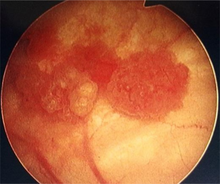

Cystoscopy: multiple papillary tumors on the right side of the posterior wall